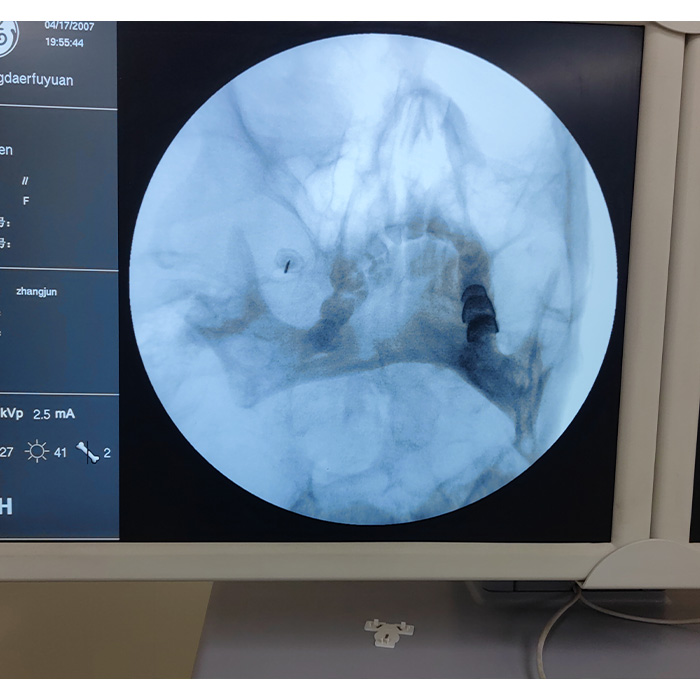

精准“看得见”,技术“摸得着”!备受期待的第十七期肩关节疼痛超声可视化精准诊疗适宜技术培训班圆满成功。 本期培训班旨在深度提升临床医师对肩关节疾病的诊疗水平,特设 “理论精讲”与“手术实操” 两大核心模块。 理论先行,夯实基础: 课程将系统梳理肩关节解剖、超声影像基础及常见病、疑难病的超声诊断思路,让您对疾病本质有更透彻的理解。 实操为重,手传心授: 培训班的重头戏在于高强度、沉浸式的手术实操。学员将在资深导师“手把手”指导下,在标准化模型及特邀标本上进行超声引导下穿刺、注射、神经阻滞及针刀治疗等关键技术的全程演练,将理论转化为稳定的肌肉记忆,真正掌握可视化精准操作的精髓。 名额有限,诚邀各位骨科、疼痛科、康复科及超声科同仁踊跃参与,共同推动肩关节诊疗技术的规范化与精准化发展!